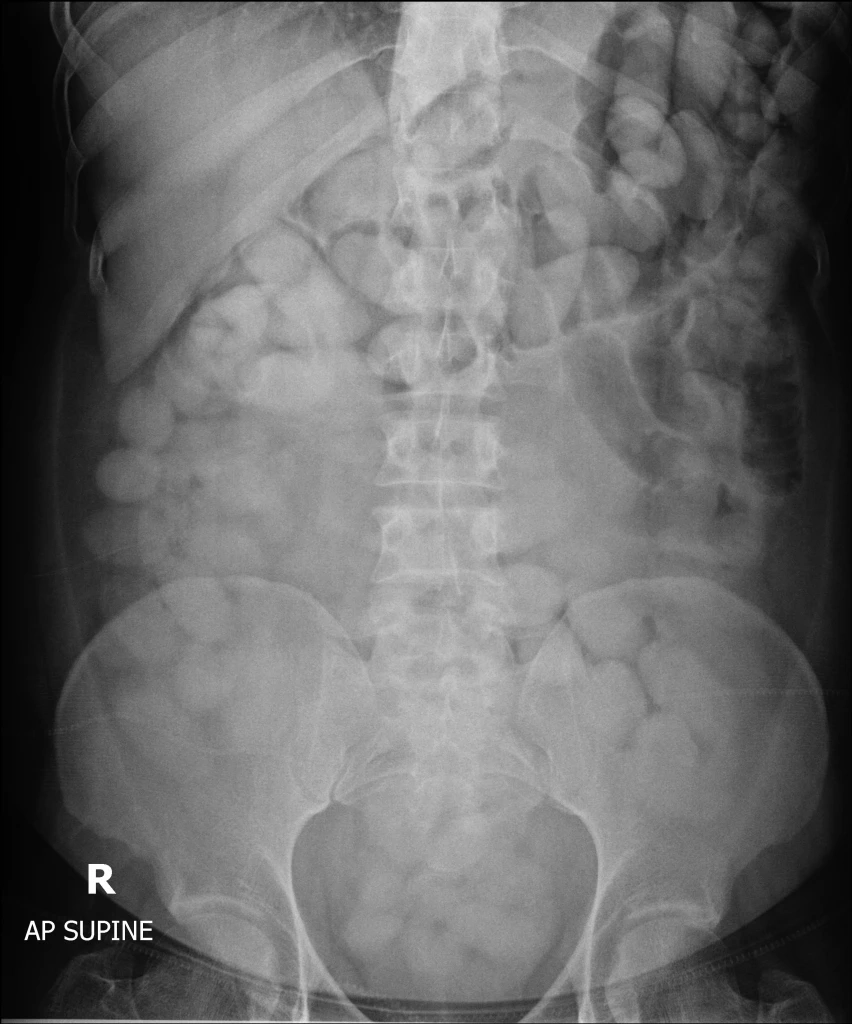

กระทั่งพบสิ่งแปลกปลอมจำนวนมาก รูปร่างทรงกลม และทรงรีอยู่ในช่องท้อง จนสุดท้ายชายต้องสงสัยยอมรับสารภาพว่า ได้กลืนยาเสพติดเข้าไป โดยพบว่าเป็นโคเคนจำนวน 115 ก้อน น้ำหนักรวมสิ่งห่อหุ้ม 1.49 กิโลกรัม มูลค่า 4.47 ล้านบาท